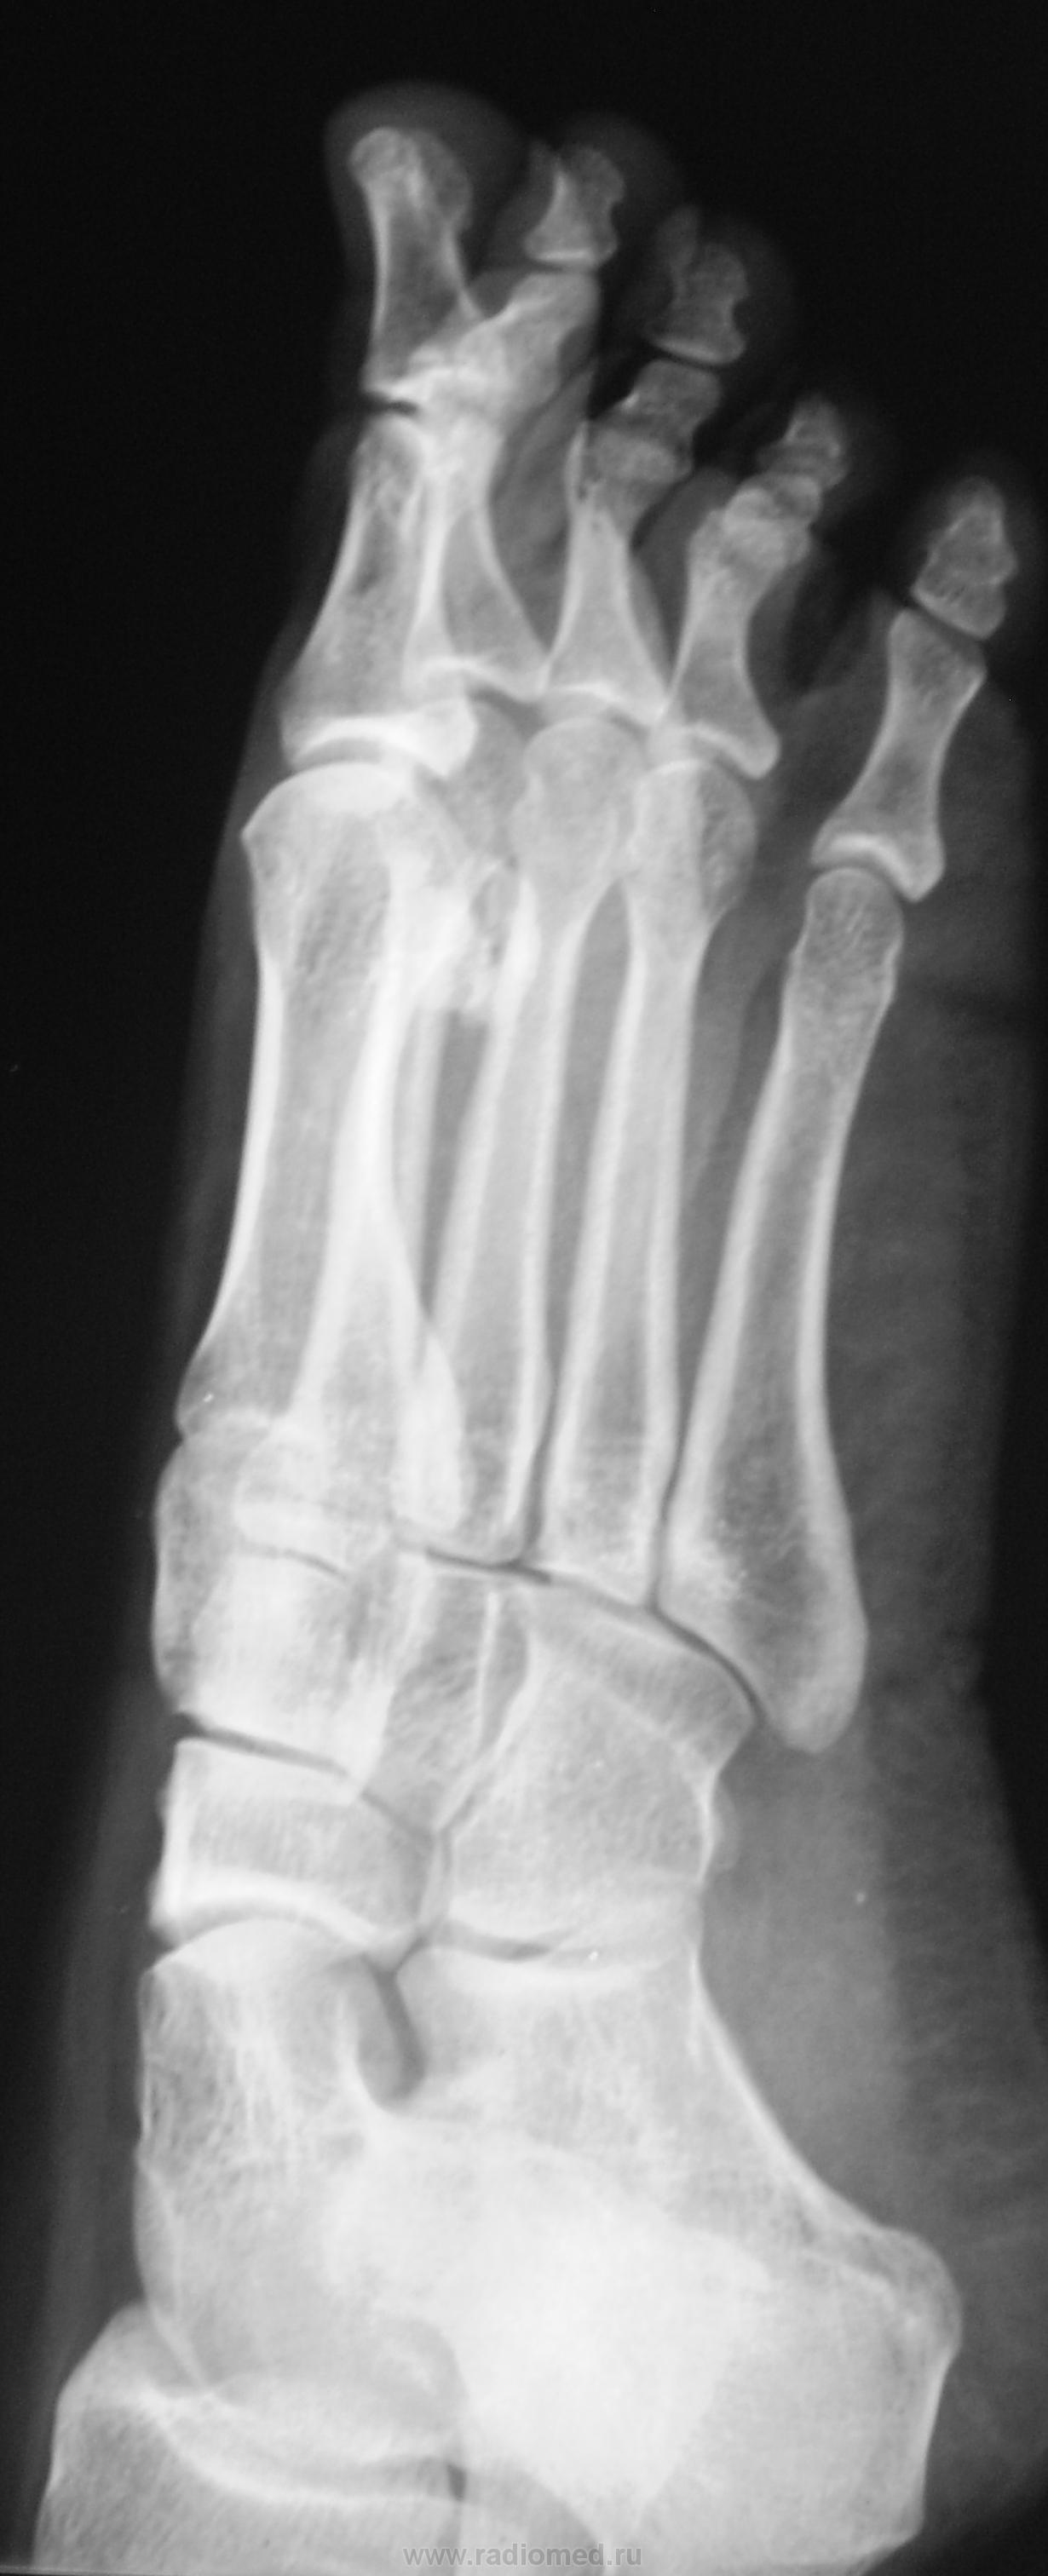

Молодая женщина. Беспокоят боли в ступнях по подошвенной поверхности, больше слева.

Правая стопа сделана больше для сравнения.

Остеохондропатия сесамовидной кости 1 пл/фал.сустава левой стопы.

Весьма патогномоничной является рентгенологическая картина третьей стадии заболевания - стадии фрагментации. Пораженный отдел кости уже не дает гомогенной тени, а состоит из нескольких темных бесструктурных изолированных фрагментов неправильной формы. Светлые участки, на фоне которых видны эти фрагменты, соответствуют разрастаниям соединительной ткани и хряща между некротическими массами. Высота пораженного отдела кости уменьшается. Длительность третьей стадии составляет от полугода до двух с половиной лет, а иногда и более. Вероятно Валентин Львович, дама не сидит, а ходит, постоянная нагрузка веса тела делает свое дело.

Фрагменты с увеличением.

"На рентгенограмме-типичная дезорганизация структурного рисунка несколько иногда увеличенной косточки с фрагментацией её тени.Регенеративные явления выражены незначительно,полного восстановления стуктуры не бывает"-С.А.Рейнберг т2 стр286.      (несколько иногда( в тексте))-это вероятно в данном случае.

несросшийся перелом сесамовидной слева